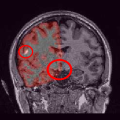

Once the reduced FOV images are available, the proposed pMRI 4D-UWR-SENSE algorithm and its early UWR-SENSE version have been utilized in a final step to reconstruct the full FOV EPI images and compared to the mSENSE Siemens solution. For the wavelet-based regularization, dyadic Symmlet orthonormal wavelet bases [48] associated with filters of length 8 have been used over resolution levels. The reconstructed EPI images then enter in our fMRI study in order to measure the impact of the reconstruction method choice on brain activity detection. Note also that the proposed reconstruction algorithm requires the estimation of the coil sensitivity maps (matrix in Eq. (2)). As proposed in [4], the latter were estimated by dividing the coil-specific images by the module of the Sum Of Squares (SOS) images, which are computed from the specific acquisition of the -space centre (24 lines) before the scans. The same sensitivity map estimation is then used for all the compared methods. Fig. 5 compares the two pMRI reconstruction algorithms to illustrate on axial, coronal and sagittal EPI slices how the mSENSE reconstruction artifacts have been removed using the 4D-UWR-SENSE approach. Reconstructed mSENSE images actually present large artifacts located both at the centre and boundaries of the brain in sensory and cognitive regions (temporal lobes, frontal and motor cortices, …). This results in SNR loss and thus may have a dramatic impact for activation detection in these brain regions. Note that these conclusions are reproducible across subjects although the artifacts may appear on different slices (see red circles in Fig. 5). One can also notice that some residual artifacts still exist in the reconstructed images with our pipeline especially for . Such strong artifacts are only attenuated and not fully removed because of the high level of information loss at .